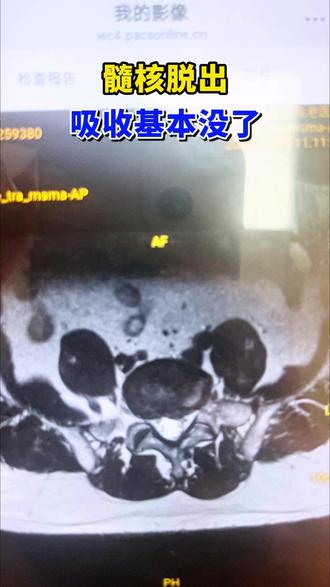

我们都知道腰椎间盘突出主要指的是纤维环破裂,髓核拖到椎管里边,压迫到神经根或者是叶毛囊,从而产生一系列的临床症状,那么这个突出的髓核如果要是不管他 会不会被人体吸收了,一般来说,如果是纤维环把它还包裹到椎间盘里边的时候,只是就像那个自行车内胎鼓出一块来,如果这种情况下的话,一般来说人体 不能把它吸收,不做手术,一直保守,最终的结果它突出的只能是越来越大啊,它不能被人体吸收, 为什么?因为这个人体免疫系统识别不到他。如果是纤维环破裂了以后,水核从这个纤维环里边跑到椎管里边拖出来了,这种情况下,随着时间的延长, 很可能被人体的免疫系统识别,就把它给清除了,这种情况下叫水合游离。什么叫游离呢?就是是通过破裂的纤维环椎间盘跑到 椎管里边,就跟小孩出门玩去了,跟家里边没有联系了啊,就一个道理,游离的这种情况下,不管他不去 手术干预,很可能时间长了,他就被人体给吸收了啊。因为我们见过这样的病例啊,一开始通过核磁发现有一块游离的血核跑到椎管里边,压迫到叶毛囊或者神经根,病人症状特别明显, 病人也不手术,他就一直硬挺着,最终过上那么半年,一复查,核磁发现那个血核没了啊,去哪了?就是被人体的免疫系统 把它给吸收了,这种情况也可能发生,所以说椎间盘一旦脱出来了,压住神经没有游离, 还是尽早积极的治疗,通过药物,通过理疗啊,实在不行赶快做手术把它给取出来啊,以免对神经造成特别严重的影响。

感觉怎么样啊?哎,那个现在啊,嗯,觉得这个右脚脚后跟有劲了。嗯 啊,但是吧,还照左脚的脚后跟还差点还差点哈啊呃,感觉疼什么的还有吗?疼倒不疼了,现在就是感觉走还是有点,就说不那么利索,你要慢点走。还行,你走快了还是不利索。嗯 好多了啊,缩小了挺挺多的,特别明显的,尤其右面那个,右面那个基本吸收掉了啊啊,右边那个,你看那个就是看那横气罐,他是不是我这个有点变形了,那个气管没事,比比以前好多了, 比以前那个右面的脱出基本没了,现在啊就剩一丢丢了,再过两个月就没了啊 你你这个基本就算恢复了啊,你看这个右侧的这个突出特特别明显,但是你那个右侧会有症状,因为他右侧的神经粘连水肿什么都有,他那个随和突出 再再吃一疗程药就没事了啊。行行,没问题啊,好吧。嗯,你这个算是恢复了已经啊,空下体重以后啊,没有没有啥别的问题吧。对,挺挺就只有好转,没有别的问题啊。